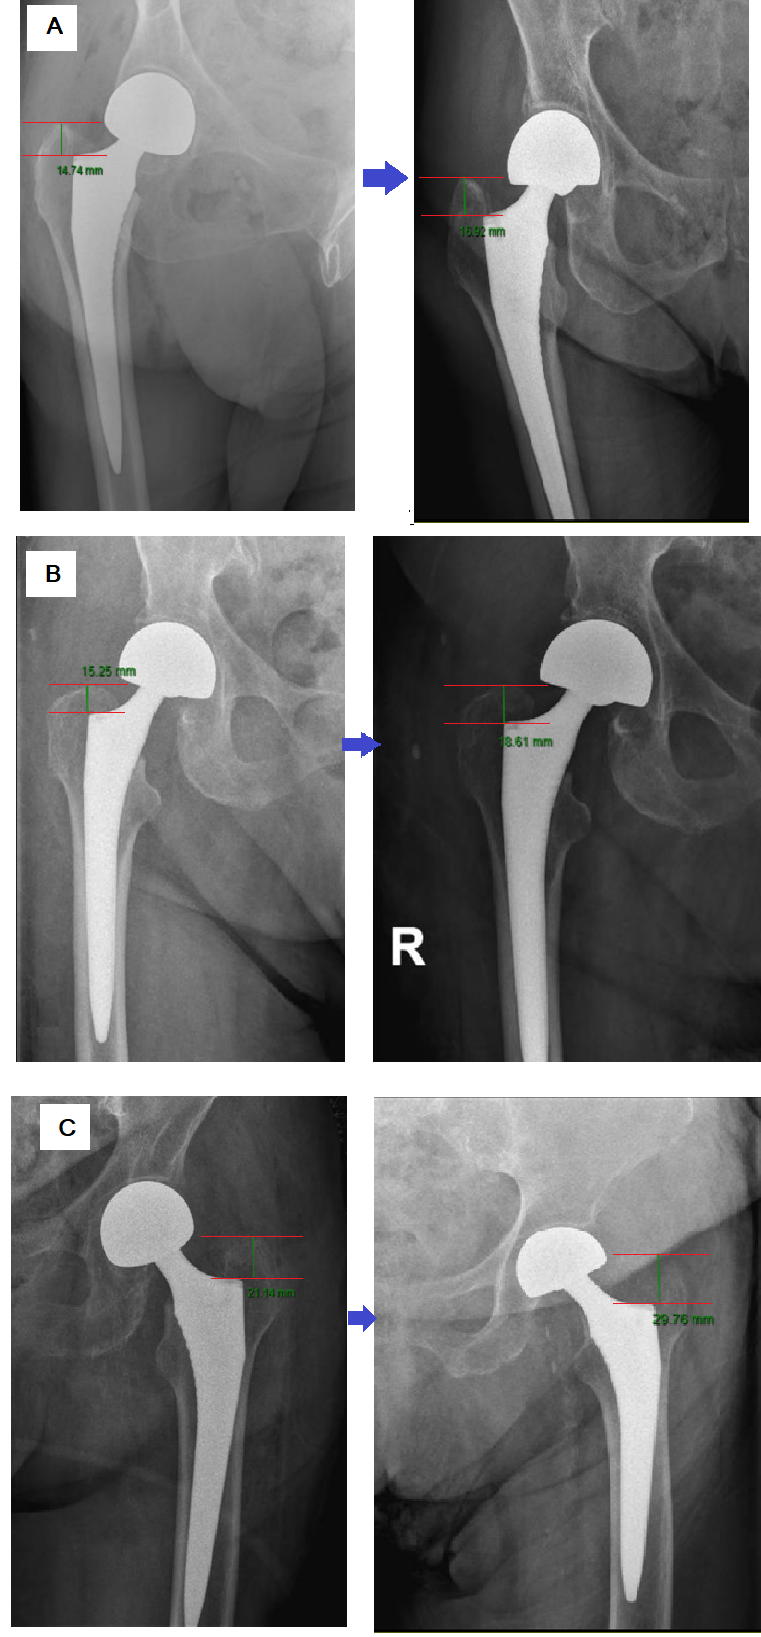

Stem subsidence was evaluated by measuring the difference in distance from the greater trochanter’s highest point to the stem shoulder perpendicular to the axis of the femur stem. This was performed using an anteroposterior (AP) radiograph of the hip or pelvis, taken between 3 weeks and 6 months postoperatively, and compared to the initial post-operative AP radiograph (Fig. 3).

Figure 3: Anteroposterior radiograph of the hip shows the determination of femoral stem subsidence by calculating the difference in distance from the greater trochanter’s highest point to the stem shoulder perpendicular to the axis of the femur stem. All the implants in this figure are Lima Corporate implants. (a) Dorr type A patient, one day after hemiarthroplasty (HA) surgery (left) and 53 days after the surgery (right), showcases a subsidence rate of 2.18 mm. (b) Dorr type B patient, one day after HA surgery (left) and 44 days after the surgery (right), showcases a subsidence rate of 3.36 mm. (c) Dorr type C patient, one day after HA surgery (left) and 37 days after the surgery (right), showcases a subsidence rate of 8.62 mm.